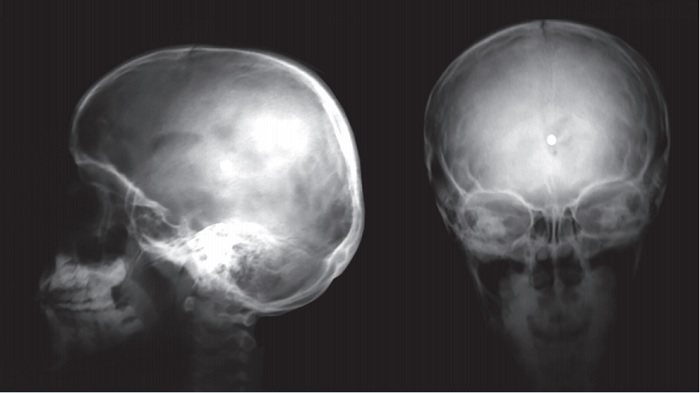

Las radiografías de cráneo (Figura 1) evidenciaron un cuerpo extraño radiopaco alojado en la parte central del interior del cráneo. La tomografía simple de cráneo (Figura 2) reportó un trayecto de entrada en línea paramediana izquierda, además de ruptura del ventrículo lateral izquierdo y alojamiento del cuerpo extraño en el tercer ventrículo. El servicio de Neurología y Neurocirugía realizó las pruebas de habilidades motoras y sensoriales, incluyendo los pares craneales, audición, habla, agudeza visual, coordinación, equilibrio, estado mental, además de cambios en el estado de ánimo y conducta durante su hospitalización, que resultaron normales en todo momento.